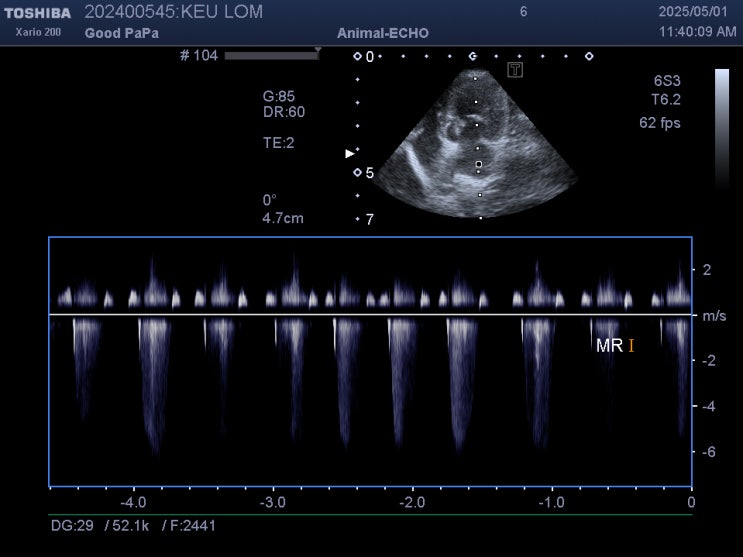

심장병 있는 강아지 이뇨제를 먹어야 하나요/ 반려견 울혈성 심부전은 어떻게 알 수 있나요 / 강아지 심장병 단계가 중요한가요 / ACVIM 미국 심장 수의내과학회 가이드라인 5단계

안녕하세요~ 굿파파 수의사입니다. 날씨가 이제 여름이네요~ 올해 윤달이 여름이라 ~ 더위가 길다고 합니다...